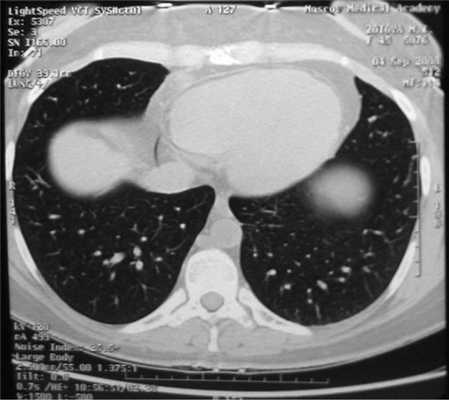

Все больные были разделены на группы в зависимости от размера очагового образования: 1-ю группу (диаметр ООЛ 0,5-1; рис. 1) составили 9 мужчин и 14 женщин, 2-ю группу (диаметр ООЛ 1-2 см; рис. 2) - 30 мужчин и 13 женщин, 3-ю группу (множественные ООЛ; рис. 3) - 27 мужчин и 17 женщин.

Рис. 3. Компьютерная томограмма груди пациента 3-й группы.

У 9 (20,4%) пациентов 3-й группы были выявлены злокачественные поражения легких, у 10 (22,7%) - диссеминированный туберкулез, у 20 (45,5%) - саркоидоз, что потребовало незамедлительного лечения в специализированных стационарах.